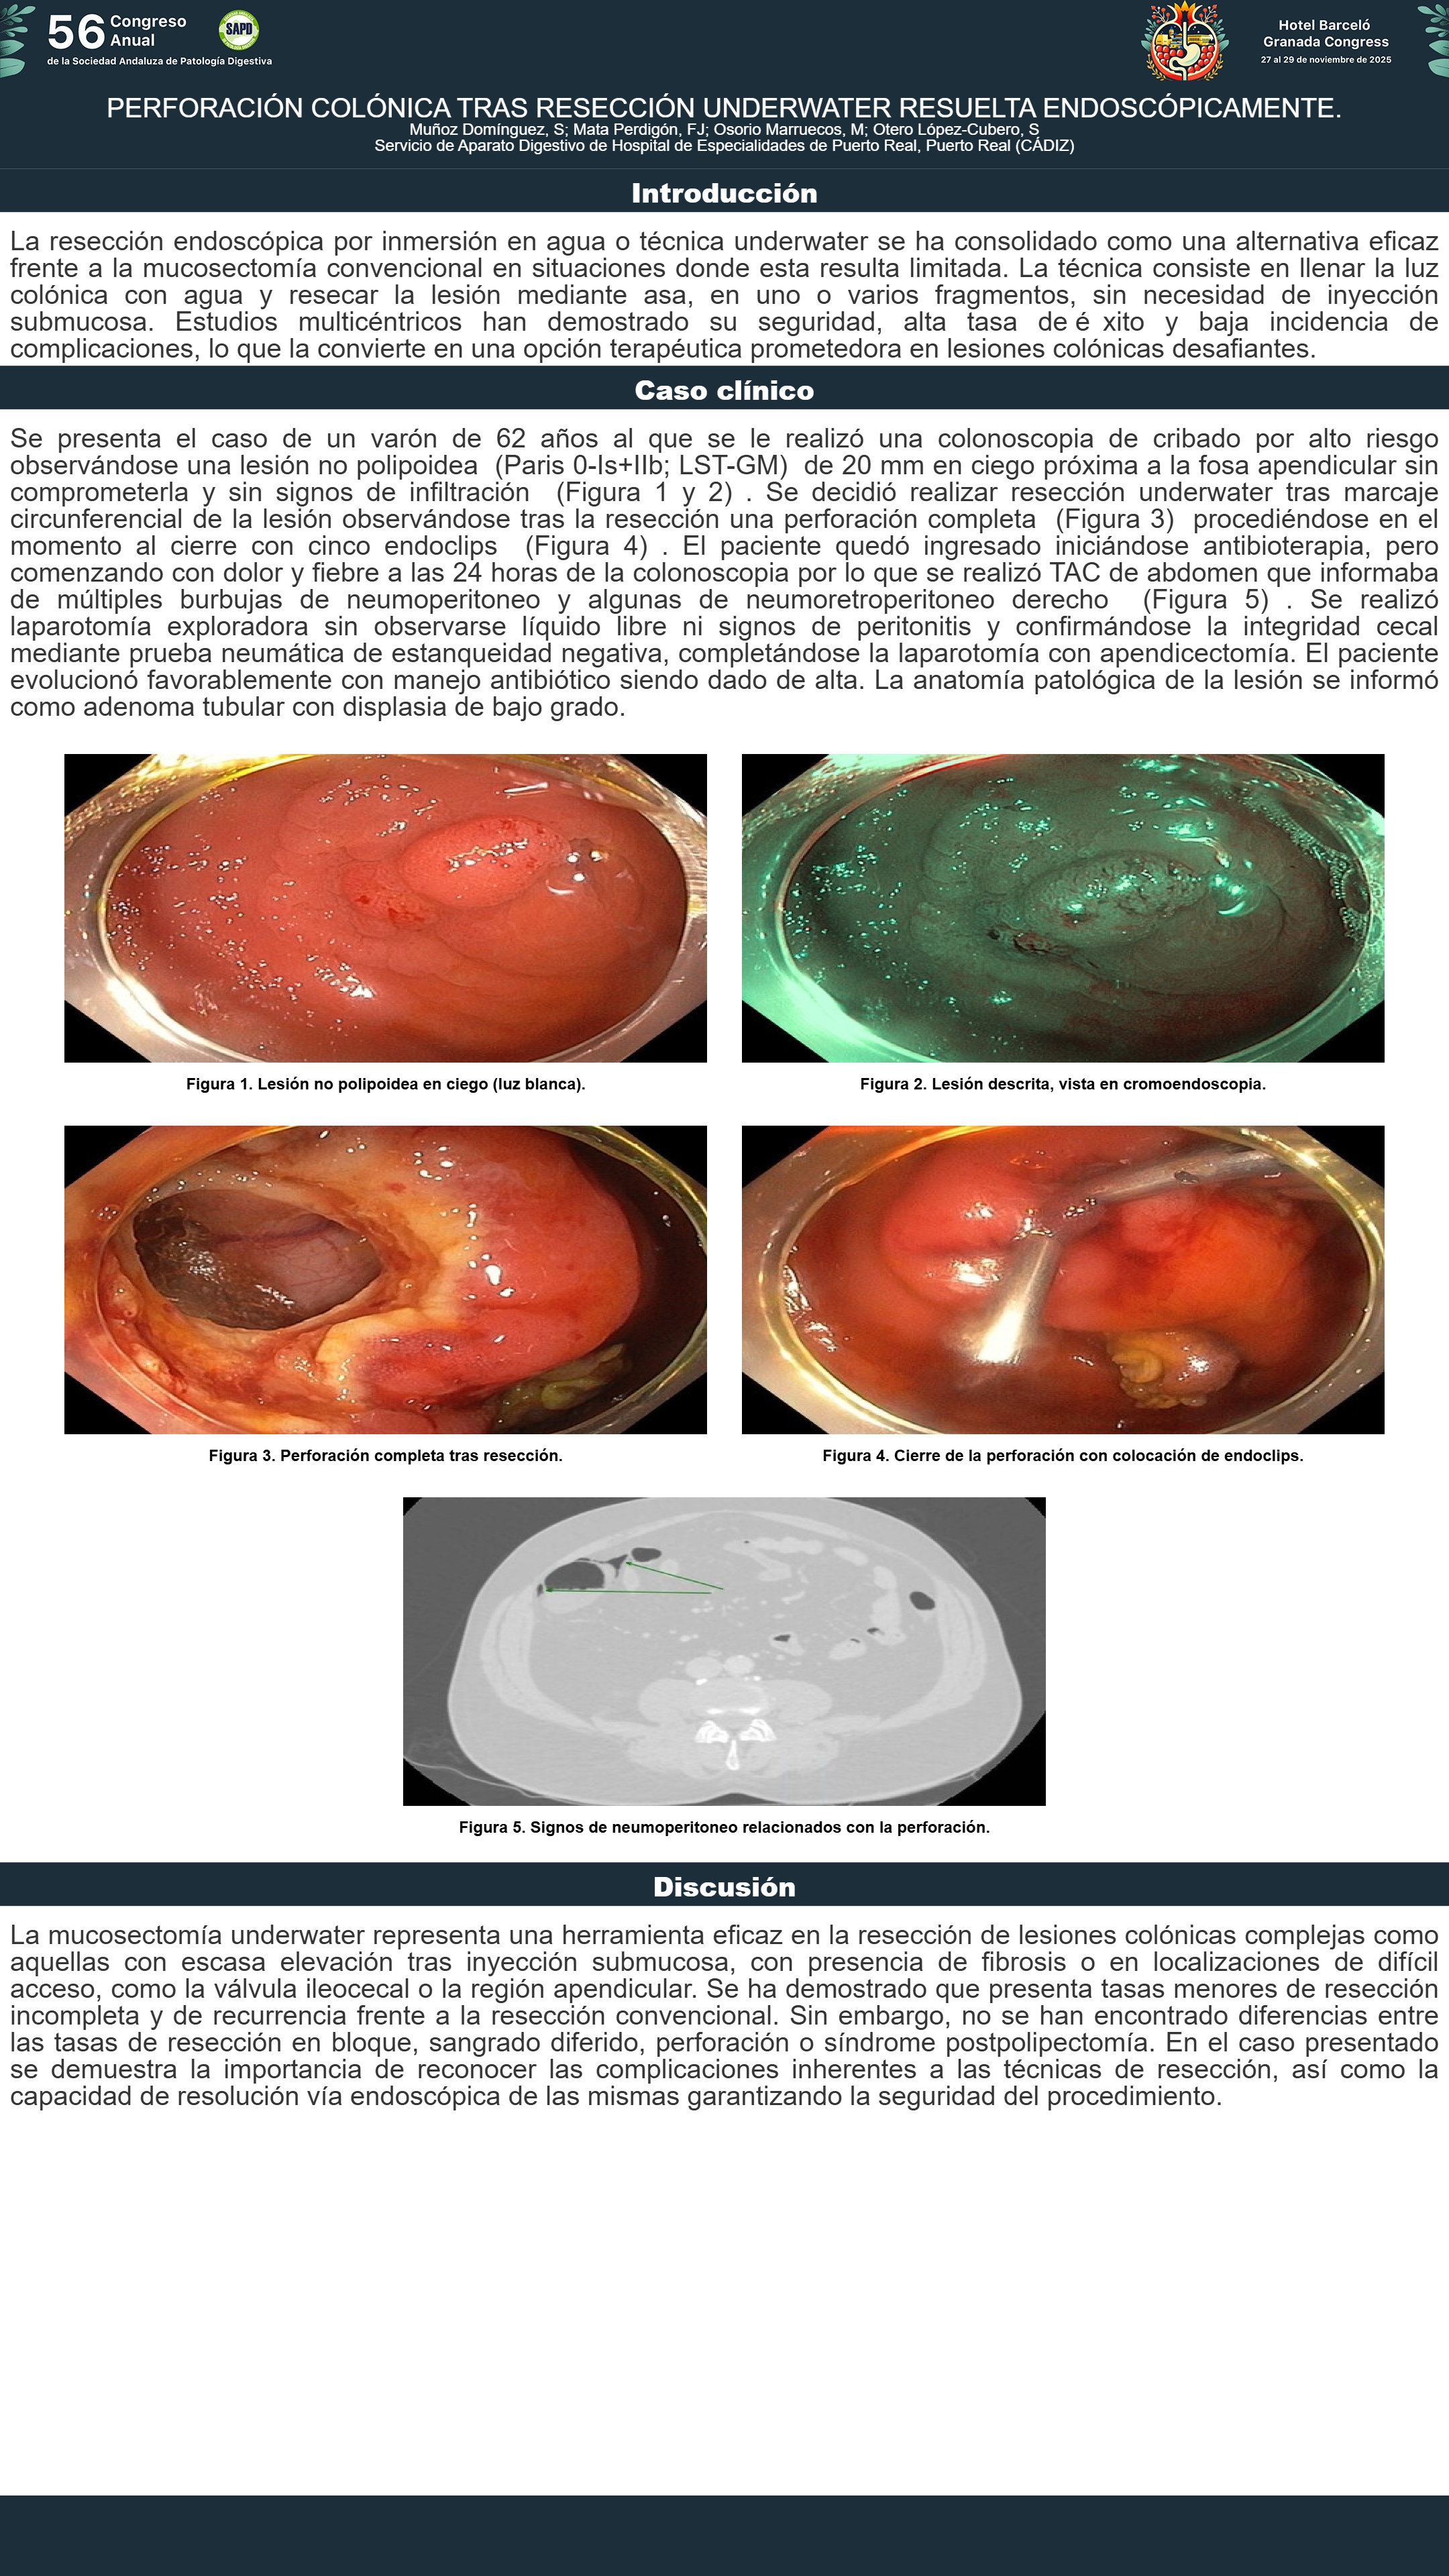

[CP-020] PERFORACIÓN COLÓNICA TRAS RESECCIÓN UNDERWATER RESUELTA ENDOSCÓPICAMENTE.